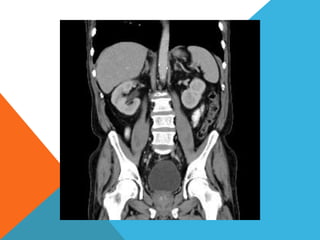

El paciente presentó síntomas de sangrado digestivo y pérdida de peso. Exámenes revelaron gastritis crónica asociada a H. pylori. Un tumor fue descubierto en una colonoscopia normal. La cirugía removió un tumor fibroide solitario, una rara neoplasia mesenquimal que usualmente crece lento y tiene bajo potencial de malignidad. El pronóstico después de la remoción quirúrgica es generalmente bueno.